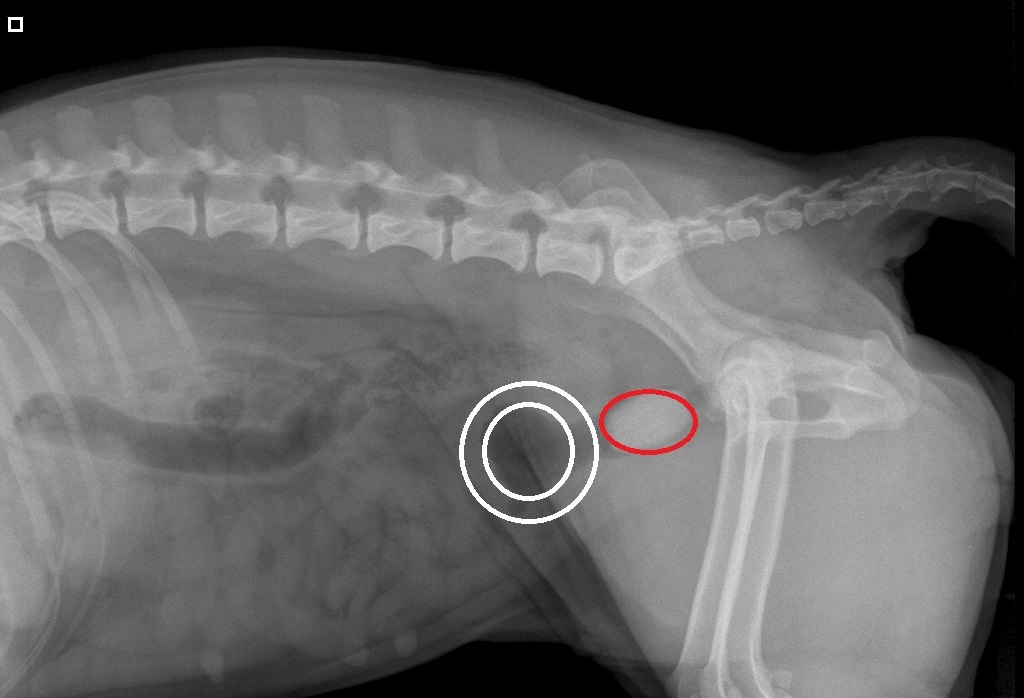

Röntgenfoto van Yvi:

A: blaas

B: de steen

De blaas heeft een erg dikke wand (witte cirkels)

en de steen sluit de uitgang van de blaas volledig af (rode cirkel)